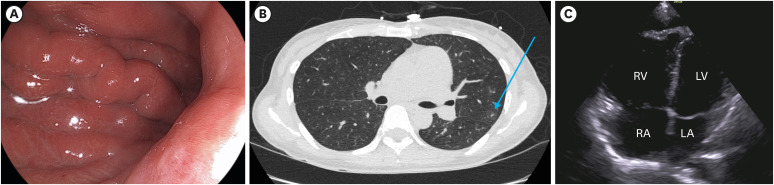

Results: The median patient age was 56 years (range, 34-66 years). In all the patients, the tumors exhibited either ulceroinfiltrative or diffusely infiltrative gross morphology. The median tumor size was 5.8 cm (range, 2.0 cm-15.0 cm). Poorly differentiated adenocarcinoma was the most common histological type (6/8, 75%), followed by signet ring cell carcinoma (1/8, 12.5%) and moderately differentiated adenocarcinoma (1/8, 12.5%). Chest computed tomography revealed ground-glass opacities (7/8, 87.5%) or tree-in-bud signs (2/8, 25.0%) without definite evidence of pulmonary thromboembolism. Disseminated intravascular coagulation was present in 62.5% (5/8) of the patients diagnosed with PTTM. C-erbB-2 was positive in one patient (1/8, 12.5%). One patient who received palliative chemotherapy after developing PTTM survived for 35 days, whereas the other 7 patients who did not receive chemotherapy after developing PTTM survived for 7 days or less after PTTM diagnosis.